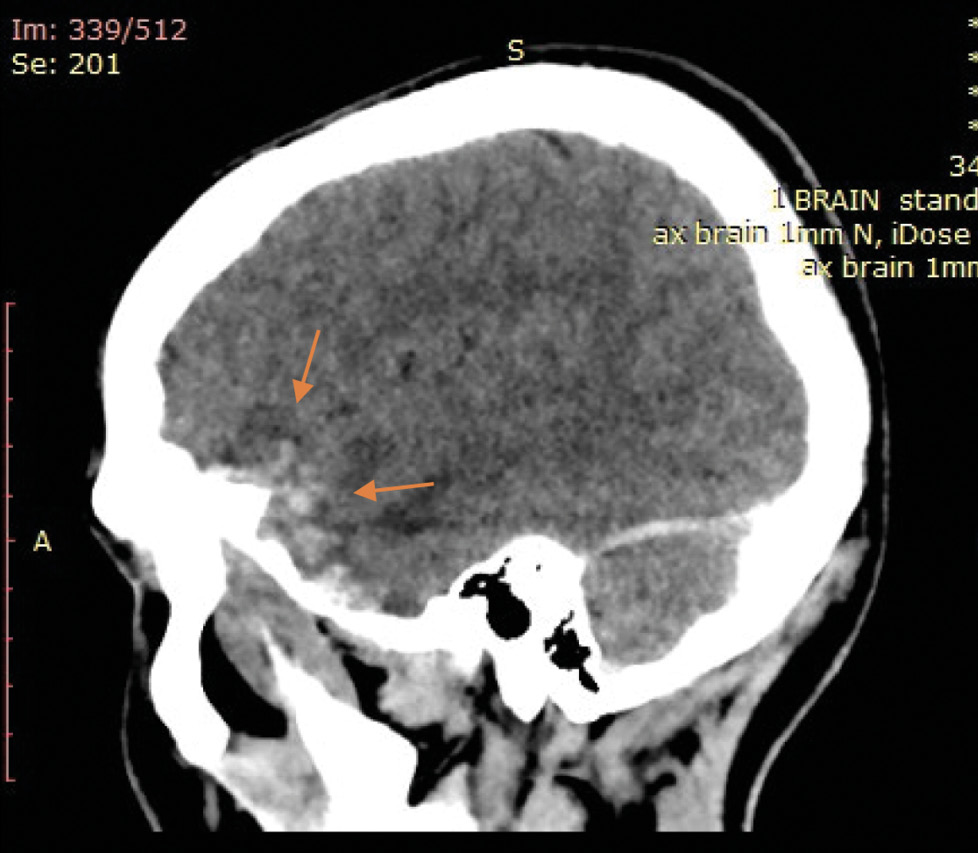

На экспертизу дополнительно представлены результаты мультиспиральной компьютерной томографии головного мозга гражданина Л., благодаря которым экспертом выявлено следующее. На серии компьютерных томограмм (с последующим 3D-моделированием) в лобно-височно-теменной области слева субдуральная гематома максимальной толщиной до 4 мм. В полюсно-базальных отделах левой височной доли определяются мелкие очаги геморрагической плотности, местами сливного характера (рис. 1, 2). Боковые желудочки симметричные. Срединные структуры мозга не смещены. Субарахноидальное пространство нивелировано слева. В бороздах мозга левой височной, левой теменной долей геморрагическое содержимое (субарахноидальное кровоизлияние), малая эпидуральная гематома правой теменно-височной области. Перелом сосцевидного отростка правой височной кости: линия перелома распространяется на пирамиду правой височной кости и заднюю стенку наружного слухового прохода (рис. 3–5). Наличие геморрагического содержимого в ячейках правого сосцевидного отростка, в антруме справа и в правой барабанной полости.

Рис. 2. Мультиспиральная компьютерная томография головного мозга: очаги ушиба головного мозга в полюсно-базальных отделах левой височной доли (стрелки) на сагиттальном срезе.

Характерная локализация и морфологические особенности внутренних телесных повреждений, выявленных при мультиспиральной компьютерной томографии головного мозга, их взаиморасположение, а также вид и локализация наружных телесных повреждений вкупе с данными материалов дела позволили прийти к следующим выводам о механизме данной травмы: ушибленная рана верхней губы слева возникла в результате ударного воздействия твёрдого тупого предмета (удар кулаком) с последующим падением и ударом пострадавшего о твёрдый тупой предмет (правая от него стена коридора) правой височной и теменной областью справа, с формированием в зоне удара головой о стену локального перелома сосцевидного отростка правой височной кости с переходом на пирамиду височной кости и заднюю стенку наружного слухового прохода, эпидуральной гематомы правой теменно-височной области, а в зоне противоудара ― очагов ушибов полюсно-базальных отделов левой височной доли, субдуральной гематомы левой лобно-височно-теменной области с субарахноидальным кровоизлиянием левой височной, левой теменной долей.